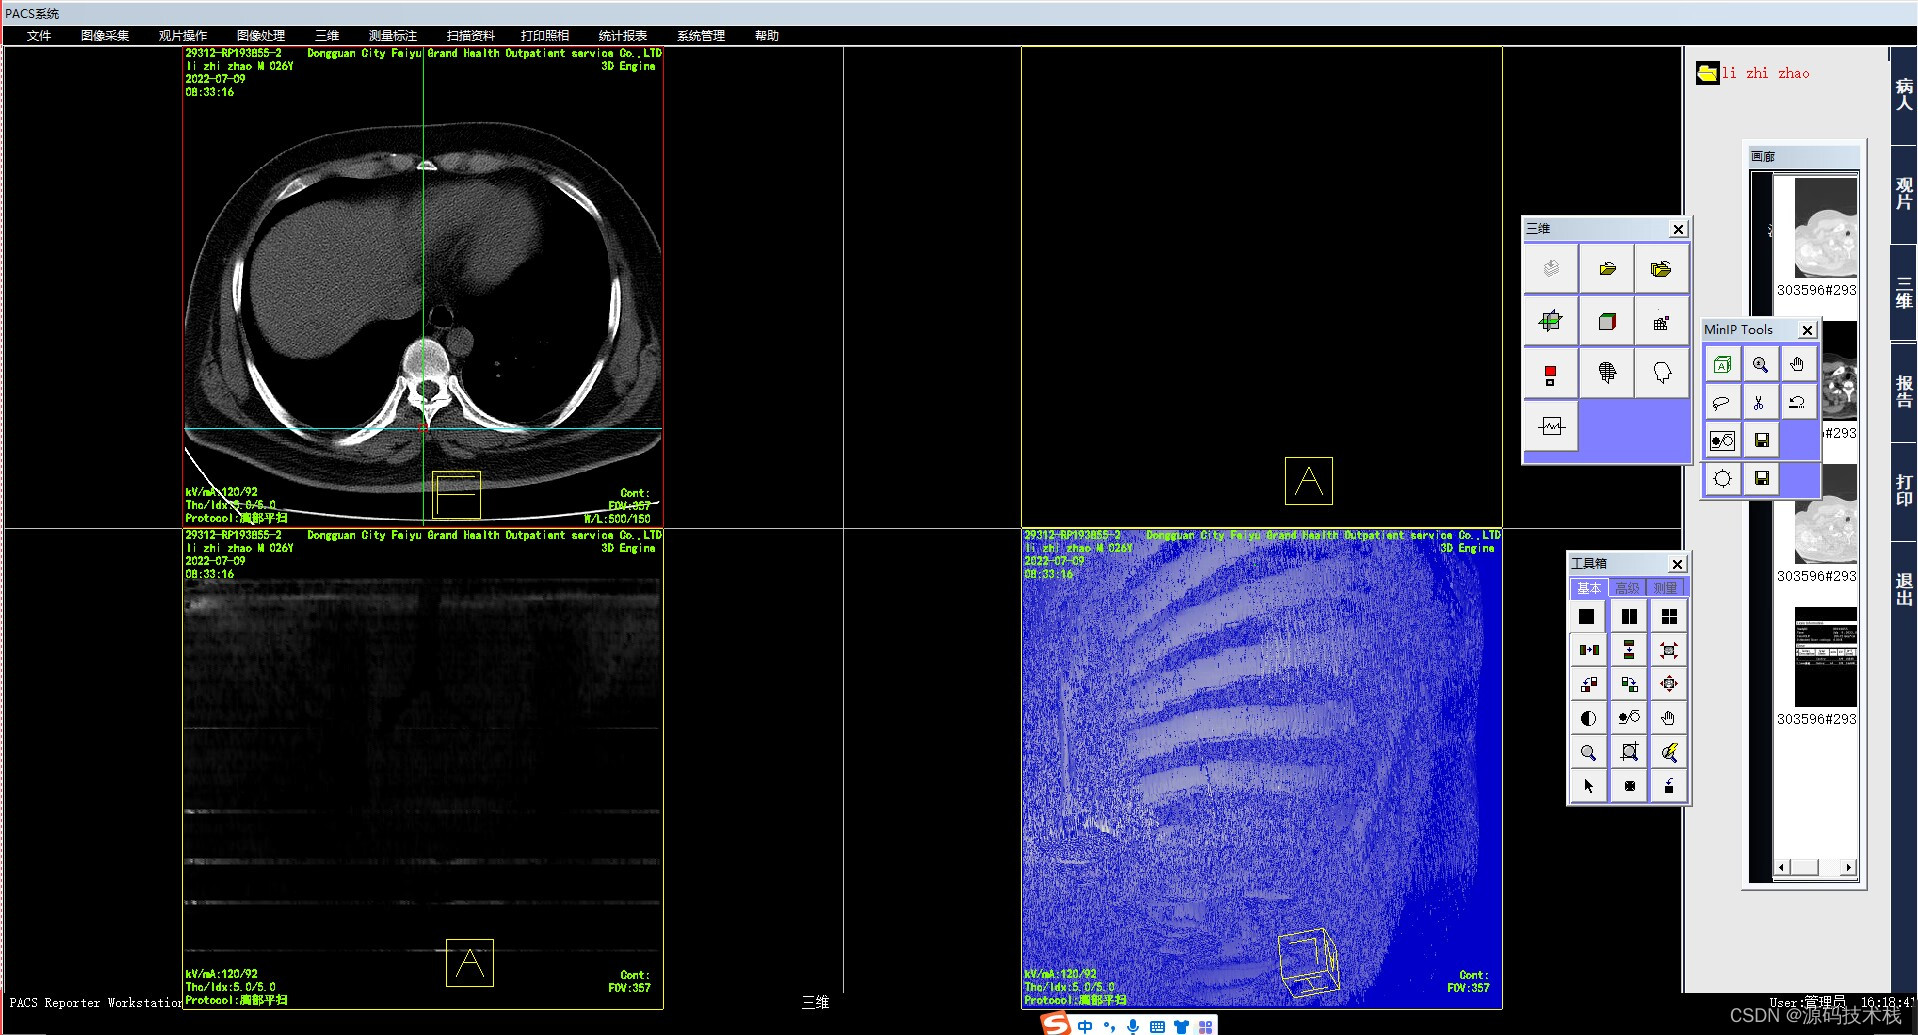

3、MinIP

MinIP(Minimum Intensity Projection),最小密度投影。和MIP正好相反,它是在某一平面方向上对

选取的三维组织层块中的最小密度进行投影,主要用于气道的显示。偶尔也用于肝脏增强后肝内扩张胆管的显示。